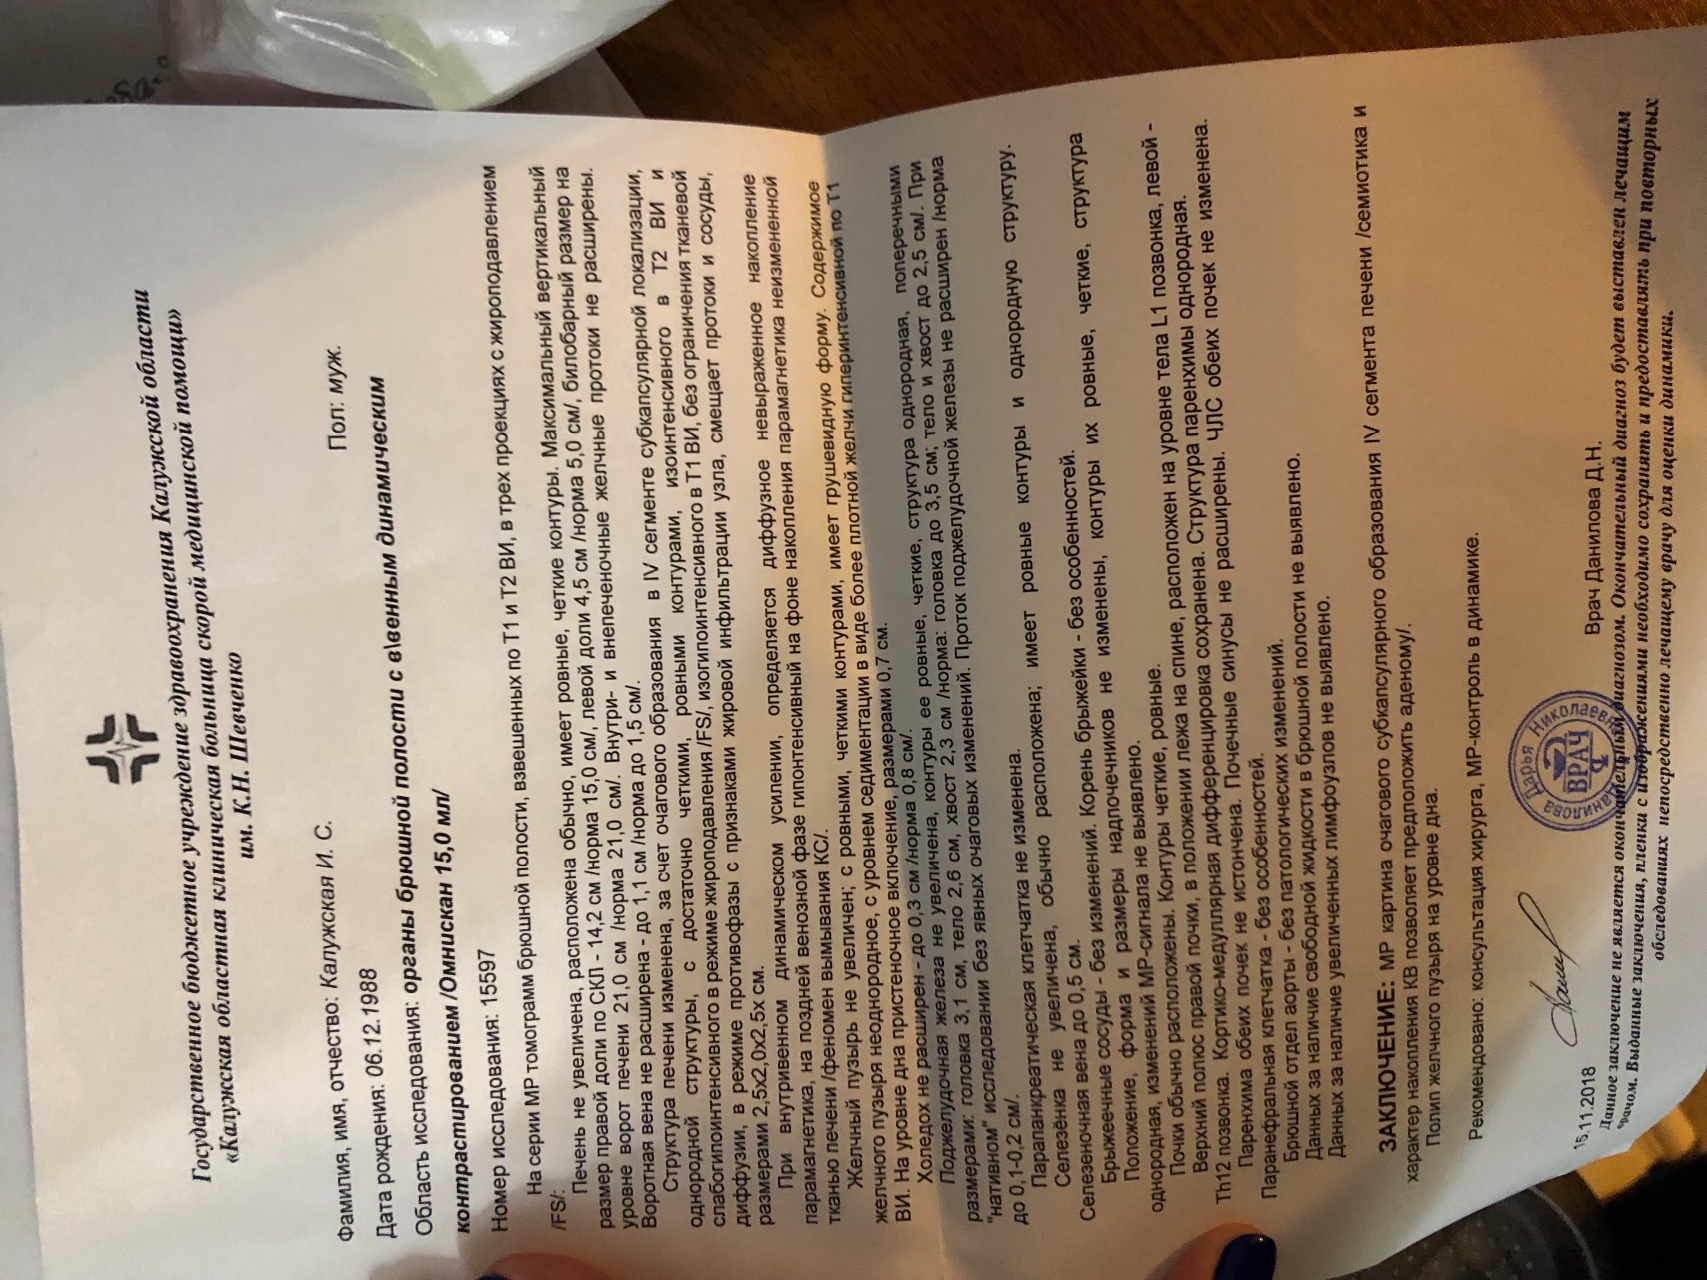

Методы динамического контрастирования печени на МРТ

Раздел: Снимки-подсказки